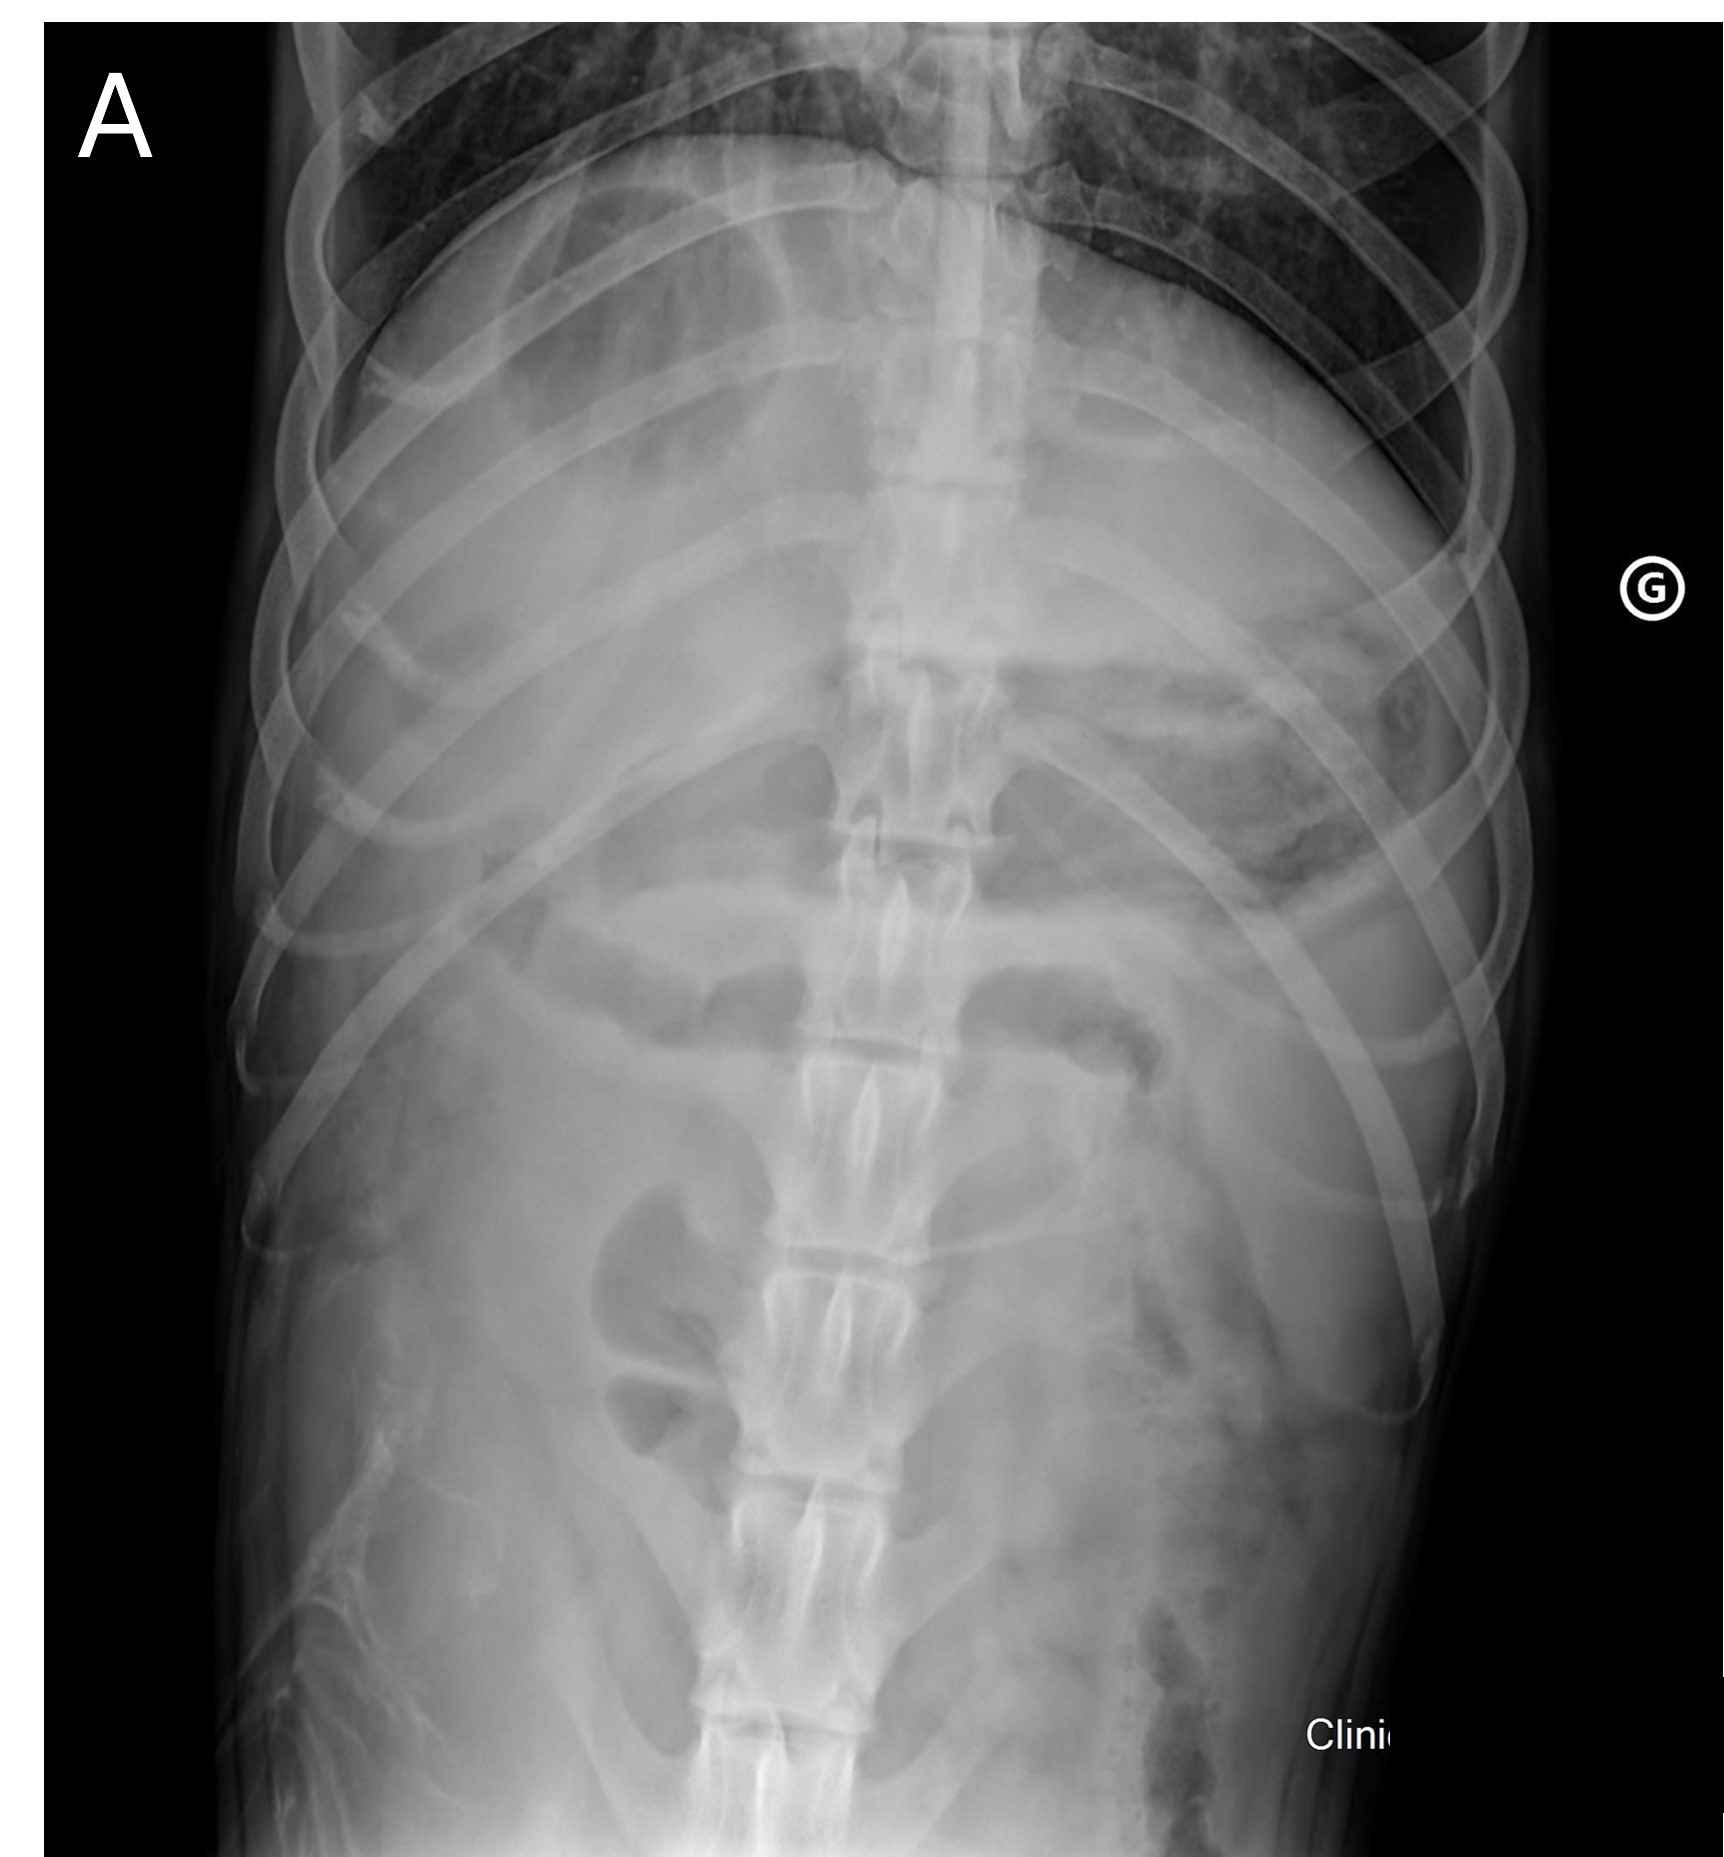

Mercredi 12 Fevrier 2025 Animaux de compagniePhoto n° 1A : Radiographie de face de l'abdomen crânial.

Un berger blanc suisse mâle entier de 6 ans est présenté pour l'exploration d'une hépatopathie dans un contexte de syndrome fébrile, polydipsie et de vomissements évoluant depuis 3 jours.